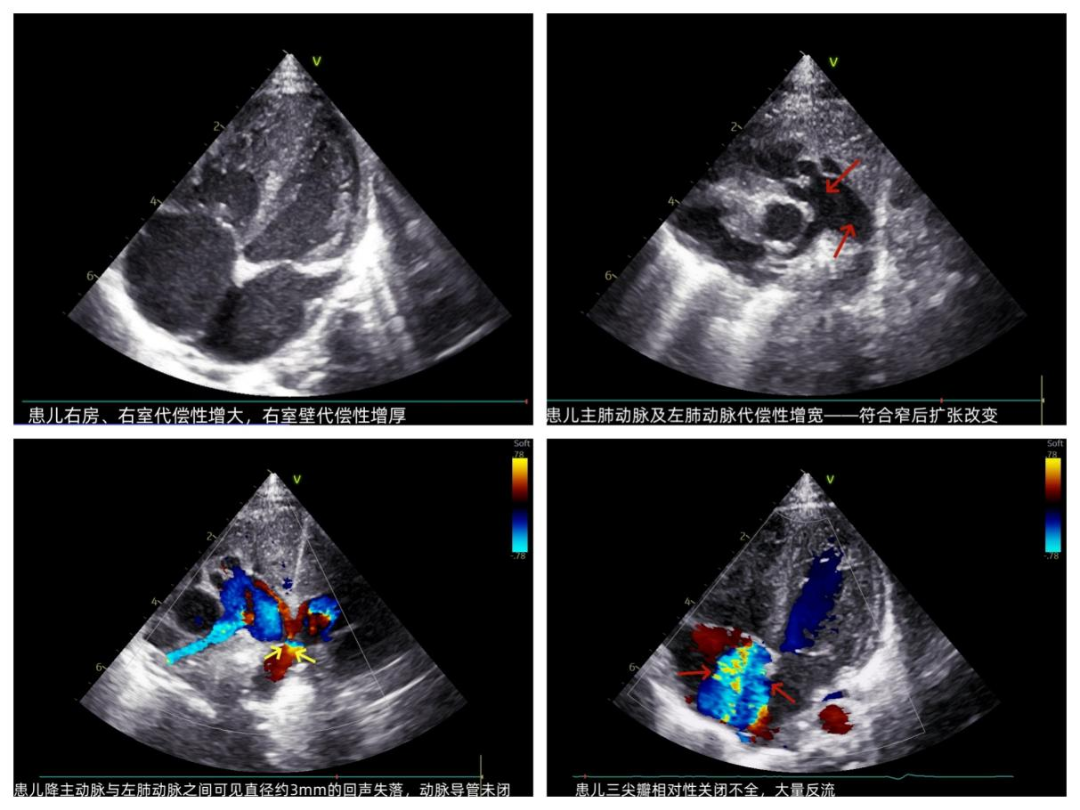

午夜12点,城市沉浸在宁静酣睡中时,呼和浩特市第一医院超声医学科灯火通明,值班医生坚守岗位随时准备出发。此时值班室电话铃响起,是新生儿监护室紧急呼叫——一名出生不到72小时的新生儿因血氧水平低,急需超声医学科进行心脏评估查找病因,值班医生推着床旁超声机一路小跑来到患儿旁开始了细致的检查,小小的身体伴随着急促的喘息,由于患儿缺氧严重、躁动不安,检查过程并不顺利,同时发现患儿肺动脉瓣异常增厚、流速增高超过高限,考虑肺动脉瓣发育畸形。超声急诊医生检查完为确保结果完整可靠,第二日交班叮嘱接诊医生要进一步检查,遂超声门诊开通“绿色通道”,确保氧气供给安全时间内完成检查,检查中发现患儿动脉导管处约3mm的窗型回声失落,伴随大血管水平左向右分流,确诊为"肺动脉瓣狭窄合并动脉导管未闭"。同时超声科为此类新生儿开辟"先心病绿色通道",为新生儿的生命安全保驾护航。

图为患儿心脏超声图像

图为患儿心脏超声图像科普知识